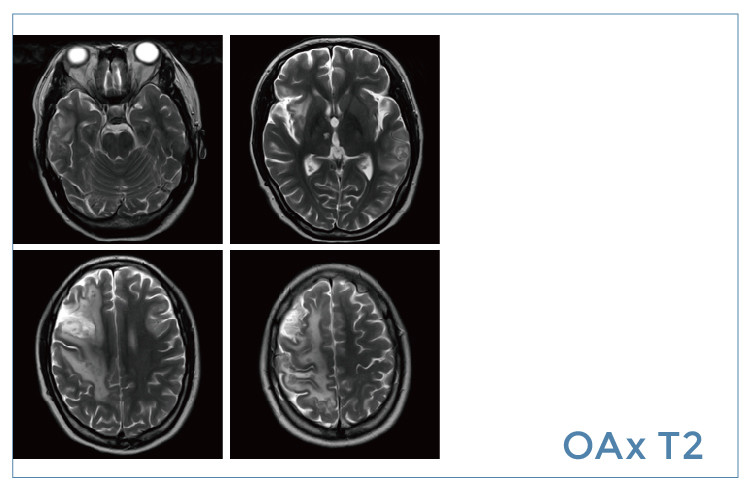

【朗润影像档案】磁共振影像病例分享(编号20191213)

【朗润影像档案】磁共振影像病例分享(编号20191206)